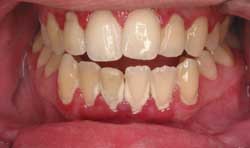

- An unhealthy smile, in which the gums pull back or recede from your teeth.

Gum disease is caused by bacteria that form into plaques on your teeth. The plaque builds up on your teeth near the gum line constantly throughout the day. The gums become swollen and red, which is the initial sign of infection. This is called gingivitis and this condition is reversible. If the plaques are not removed from the teeth on a regular basis, the bacteria move deeper into the gums progressing into an irreversible disease called periodontitis. It is at this stage when the bacteria eat away at the tissues and surrounding bone that hold your teeth in place. This stage of the disease can be arrested, but if it is not caught early enough it will result in tooth loss. Eventually, late stage periodontal disease will cause pain and your teeth will become loose.

Gum disease is treated differently for each individual case. The treatment depends on the severity of the disease as well as the location of the disease in the mouth. Treatment includes more frequent cleanings, deep cleanings called scaling and root planning, antibiotic therapy, and tooth extractions just to name a few.